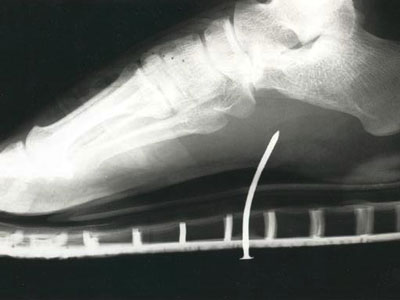

3. Người đàn ông này đã dẫm phải chiếc đinh khi đang đi dép xăng-đan: